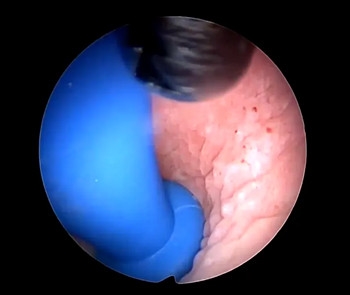

孟主任利用宫腔镜专用异物钳

钳夹住硬币轻轻转动

松动后缓慢平稳的将银币转成斜位

将它慢慢取出

术后再次进镜后见阴道中段

前后壁及侧壁粘膜均见异物侵蚀后损伤